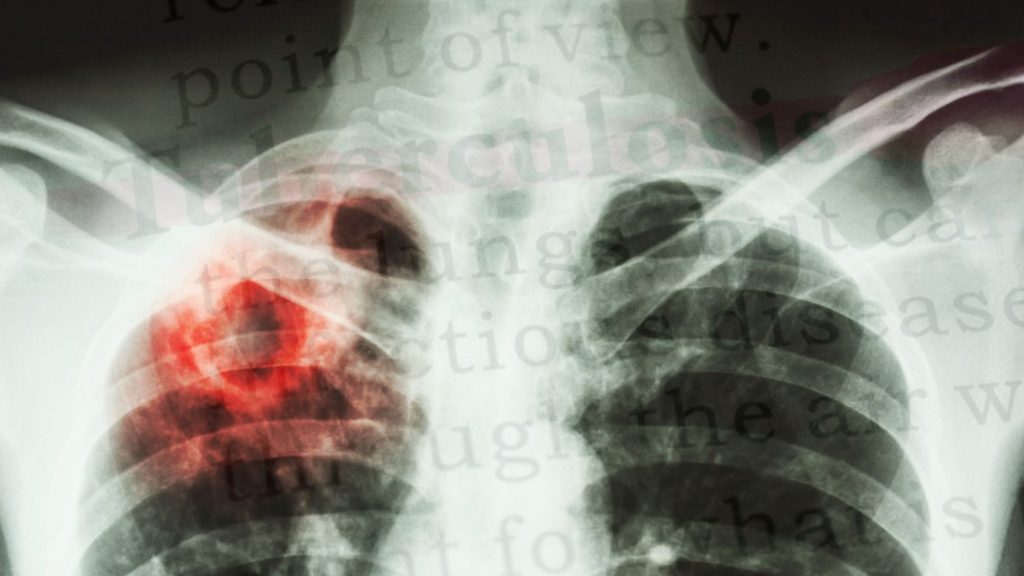

Már­ci­us 24-én, a Tuber­ku­ló­zis világ­nap­ja. Bár a tuber­ku­ló­zis első­sor­ban orvo­si keze­lést igé­nyel, a ter­mé­szet­gyó­gyá­szat kiegé­szí­tő esz­köz­ként sokat tehet a lég­ző­rend­szer támo­ga­tá­sá­ért és az immun­rend­szer erő­sí­té­sé­ért. Bol­bás Csil­la, ter­mé­szet­gyó­gyász írá­sa.